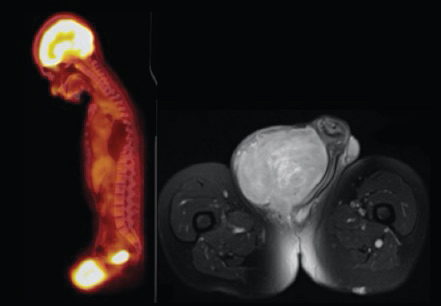

One year following initiation of pazopanib for the mediastinal mass, which had remained stable in size, a high-uptake penile mass first appeared on follow-up 18-fluoro-2-deoxyglucose (FDG) PET-CT scan, among the lumbar and sacral plexus neurofibromas. Five months later, a repeat FDG PET-CT scan revealed a significant increase in size and metabolic activity concerning for sarcomatous degeneration of a peripheral nerve sheath tumor. Urology was consulted at this time, as the patient suffered from discomfort and difficulty with ambulation. Further evaluation with pelvic magnetic resonance imaging (MRI) revealed a large 9.8 × 9.2 × 8.5 cm mass in the right perineal region near the base of the penis with areas of central necrosis, but without pelvic or inguinal lymph node involvement (Figure 1). Physical examination revealed a large, indurated mass at the right penile base, fixed to the pubis, pushing the penile shaft to the left and the right testis inferiorly.

Figure 1: PET-CT left; MRI right. View Figure 1